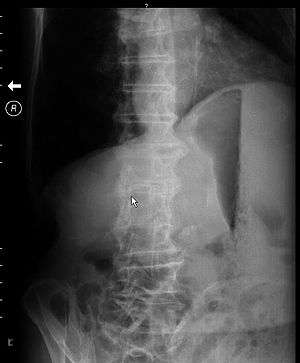

| Decubitus x-ray of abdomen of patient with gastric outlet obstruction. There is a prominent gastric air bubble, gastric air-fluid level, and a dilated stomach with particulate matter within it. | |

- A gastric fluid level may be seen which would support the diagnosis.